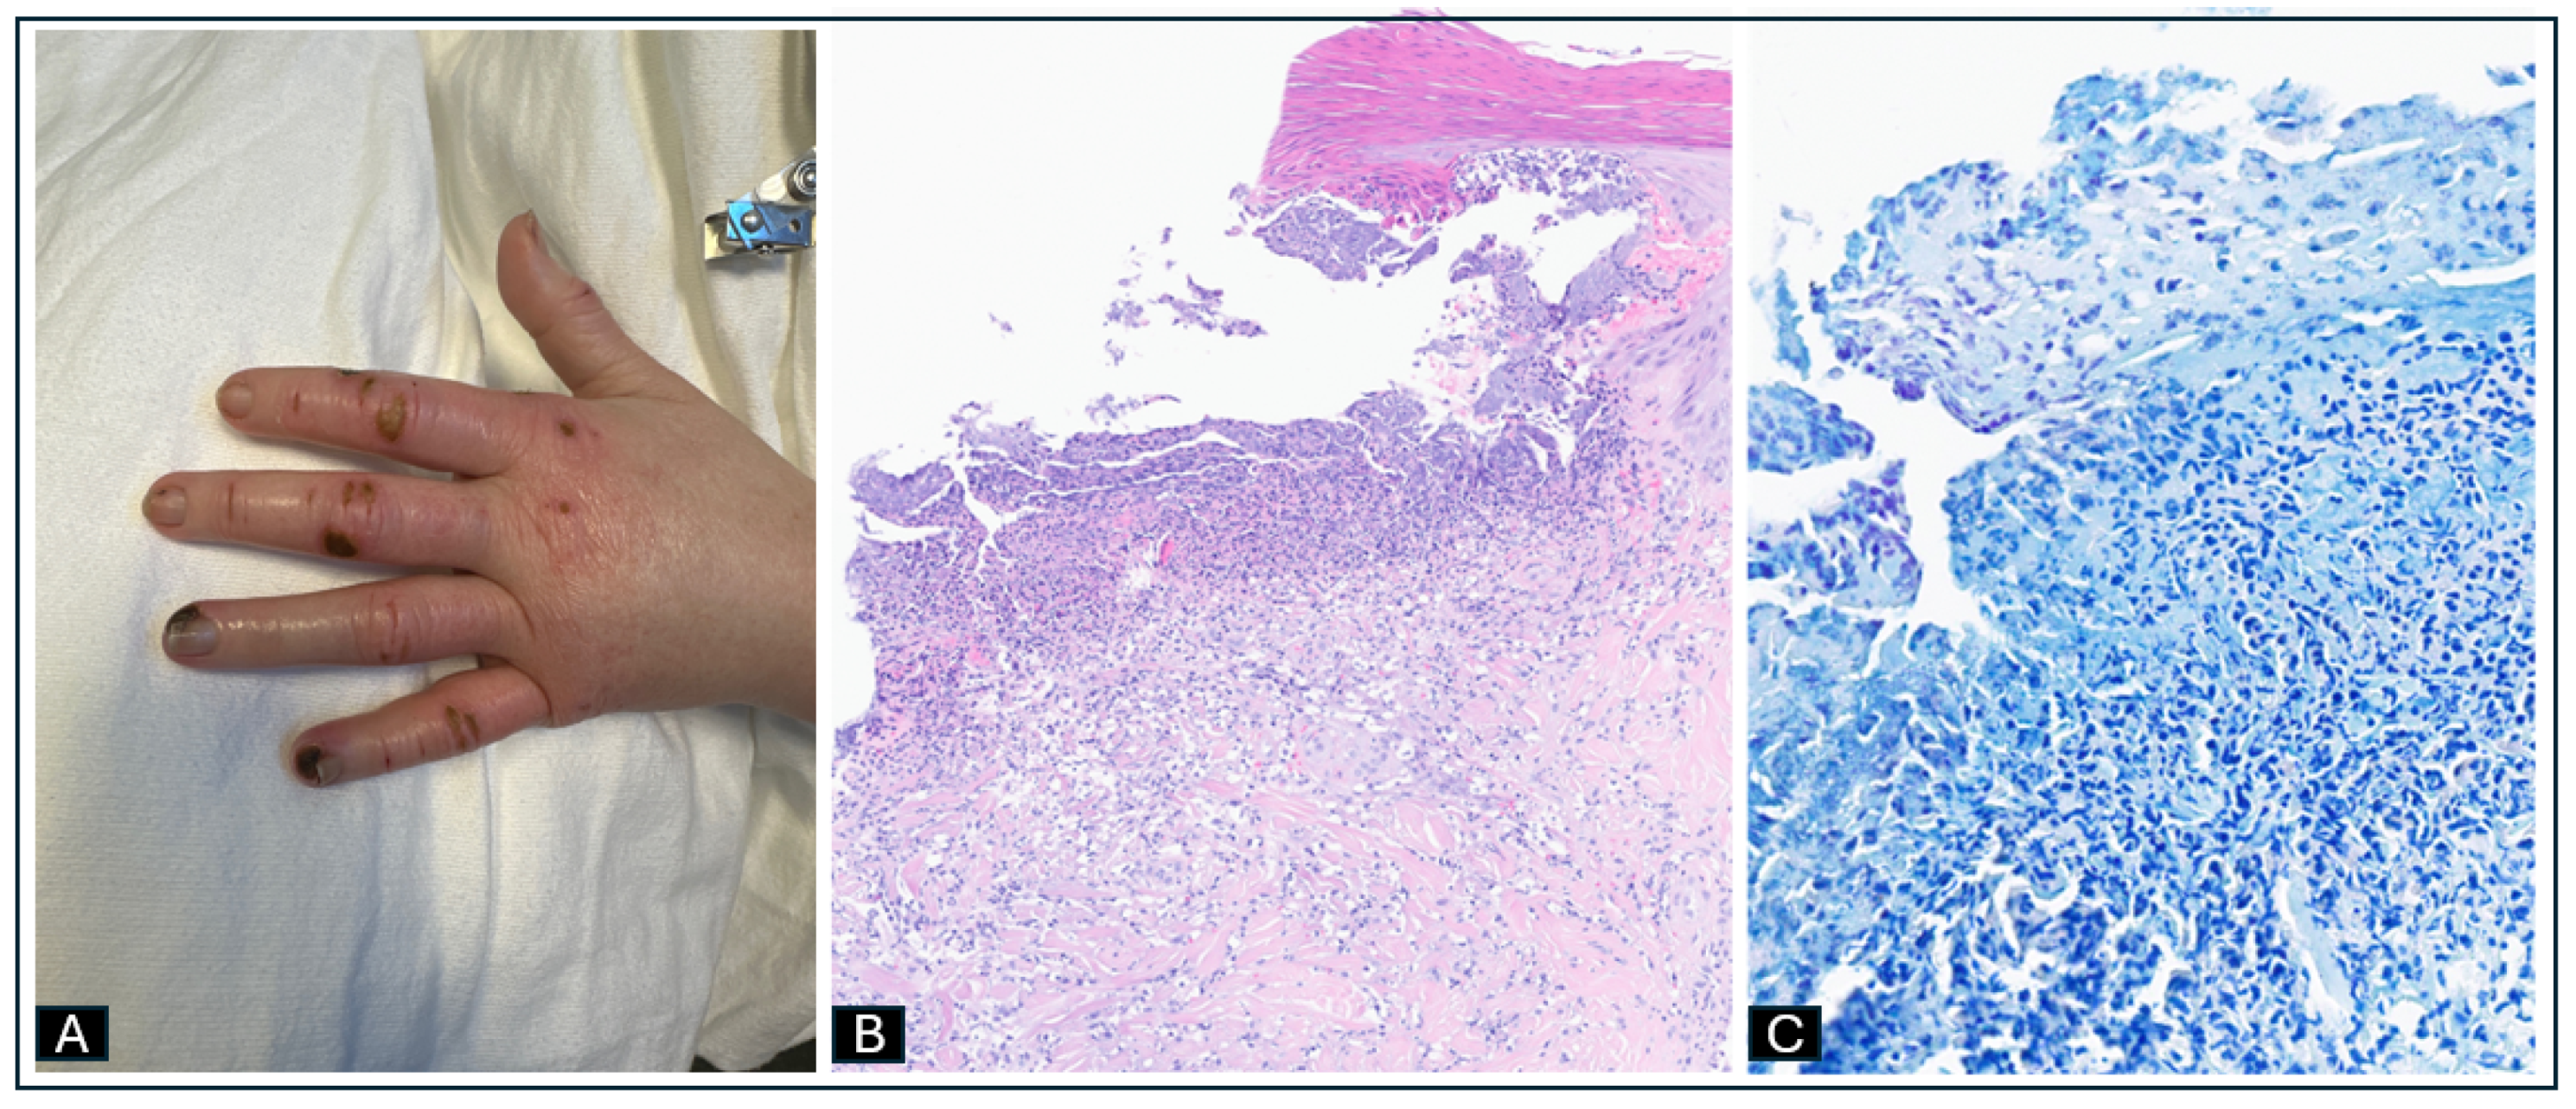

2.2. Case 2: Disseminated M. chelonae